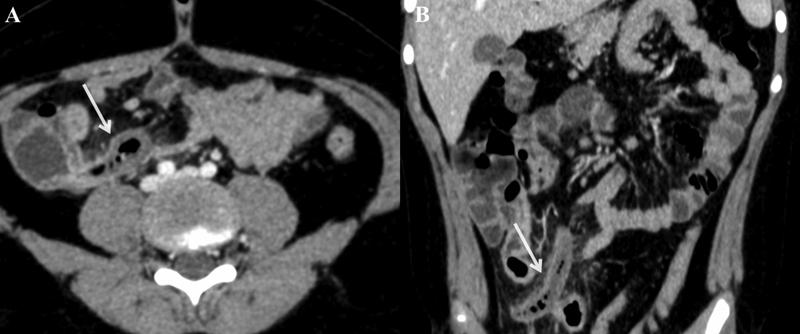

Five patients recovered well and were started on an oral diet at a mean duration of 35 hours after surgery (range: 24–48 hours). Chemotherapy was restarted after a mean duration of 11.2 days (4–17 days) from the onset of symptoms. Patients were discharged after a mean postoperative stay of 7 days (range: 5–10 days). One patient had a delay in diagnosis due to inconclusive US findings. The patient had persistent fever with neutropenia on day 4 of admission; hence, antibiotics were upgraded, and antifungal therapy was added empirically as per the institutional policy. A CT scan conducted on day 5 due to clinical worsening and development of abdominal distension revealed the presence of appendicular perforation, which necessitated surgical intervention. The patient developed features of septic shock on postoperative day 4 requiring inotropic (norepinephrine and dobutamine infusion) support and died on postoperative day 8 due to refractory septic shock ([Table 2]). All six patients had histology-proven appendicitis with no specimen showing leukemic infiltration on hematoxylin-eosin staining and immunohistochemistry ([Fig. 2]).

Fig. 2Histopathological examination of the surgical specimen. (A, B) Scanner view showing mucosal ulceration (black arrow) with transmural infiltration by neutrophils along with serosal congestion in two different areas shown with normal mucosa (orange arrowhead; hematoxylin and eosin [H&E] 40X). (C) Low power view showing ulceration of mucosa (black arrow; H&E 100X). (D) High-power view showing the presence of neutrophils (black arrow) in muscularis propria of appendix (H&E 400X).

Fig. 2 Histopathological examination of the surgical specimen. (A, B) Scanner view showing mucosal ulceration (black arrow) with transmural infiltration by neutrophils along with serosal congestion in two different areas shown with normal mucosa (orange arrowhead; hematoxylin and eosin [H&E] 40X). (C) Low power view showing ulceration of mucosa (black arrow; H&E 100X). (D) High-power view showing the presence of neutrophils (black arrow) in muscularis propria of appendix (H&E 400X).